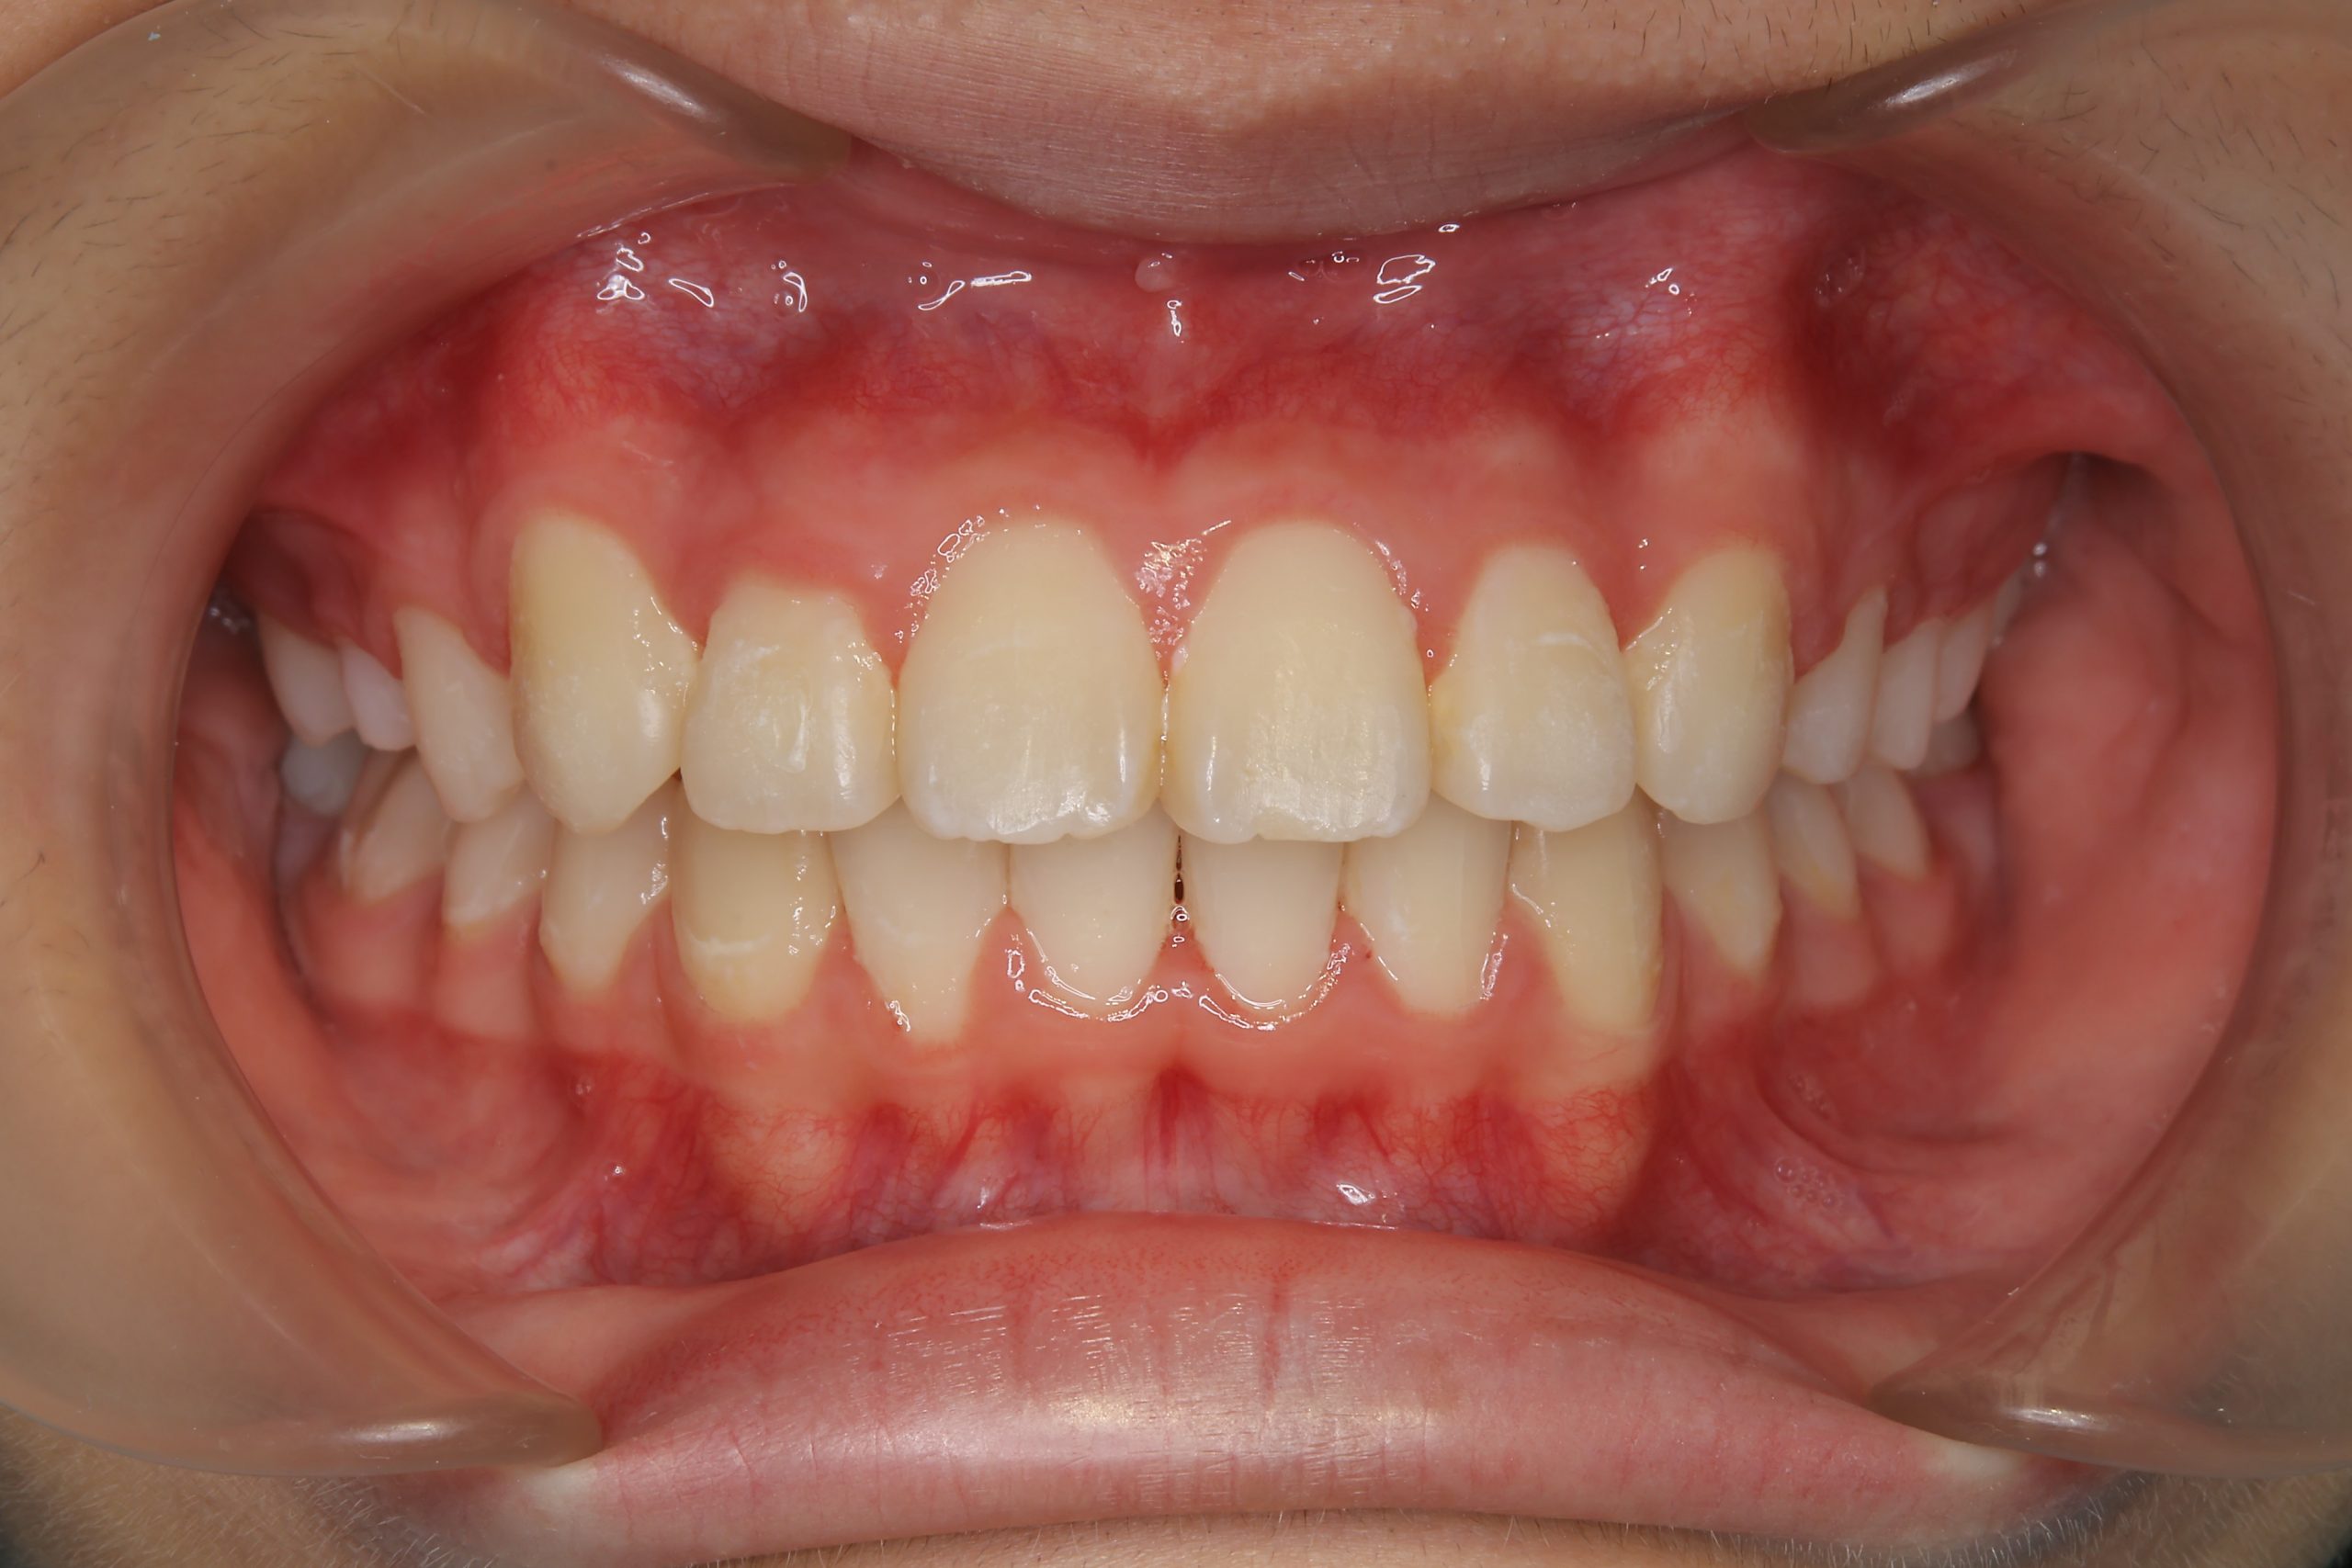

ビフォー

アフター

主訴 下顎が出ている

施術内容 MSEと下顎リンガルアーチを用いて上下顎骨を拡大した。

その後マルチブラケット装置を用いて非抜歯で歯牙を配列し、良好な咬合を獲得した。

治癒期間 1年5か月間